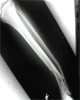

Pre

Op

Closed comminuted pilon frature ankle in 52year old male folllowing a fall from height